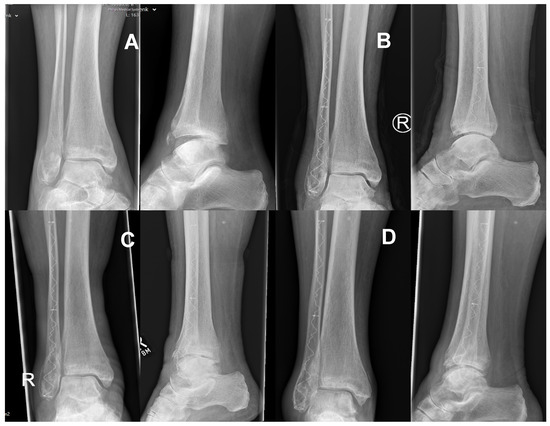

2.2. Surgical Technique and Postoperative Therapy

3.3. Radiological Follow Up

- Zyskowski, M.; Crönlein, M.; Heidt, E.; Biberthaler, P.; Kirchhoff, C. Osteosynthesis of distal fibular fractures with IlluminOss: Video article. Unfallchirurg 2017, 120, 6–11. [Google Scholar] [CrossRef][Green Version]